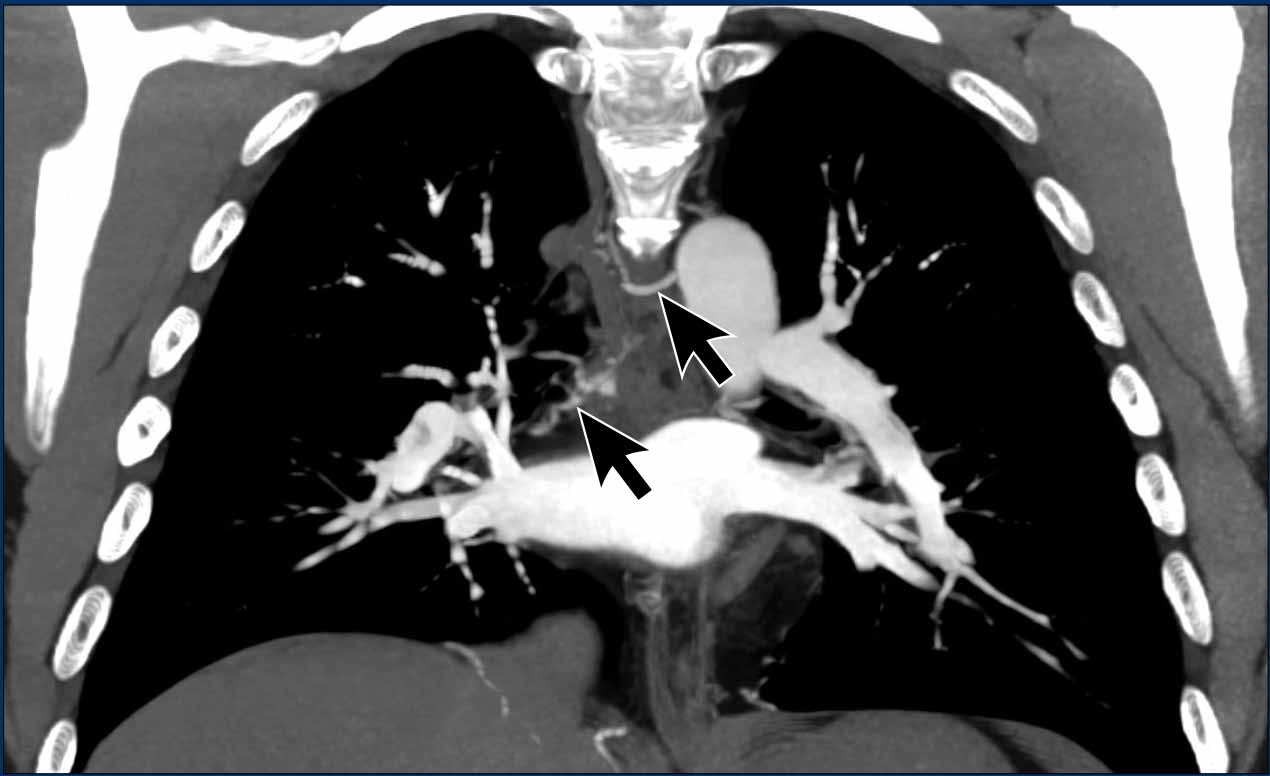

Bronchial artery hypertrophy in CTEPH

Bronchial artery dilatation further suggests longstanding abnormalities in pulmonary arterial flow, with recruitment of systemic arterial circulation as an alternative source of pulmonary perfusion.

Image

Dilatation of bronchial arteries (arrows) in a patient with PH.

Notice the widened pulmonary arteries.